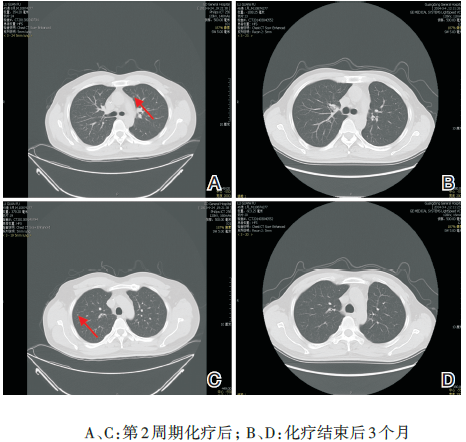

鼻咽+颈部MRI(2013-07-31)示:(1) 鼻咽左侧壁可见一椭圆形软组织肿块影, 最大径约31 mm× 19 mm, 肿块累及头长肌、腭帆提肌、腭帆张肌、翼突。左侧咽隐窝及咽鼓管咽口变窄、消失, 右侧咽隐窝及咽鼓管清晰。双侧颈部Ⅱ 、Ⅲ 区见多发小淋巴结, 最大者约8 mm× 10 mm。诊断:鼻咽左侧壁肿块, 考虑鼻咽癌并累及头长肌、腭帆提肌、腭帆张肌、翼突(见图1)。

图1 鼻咽颈部MRI图像(2013-07-31)